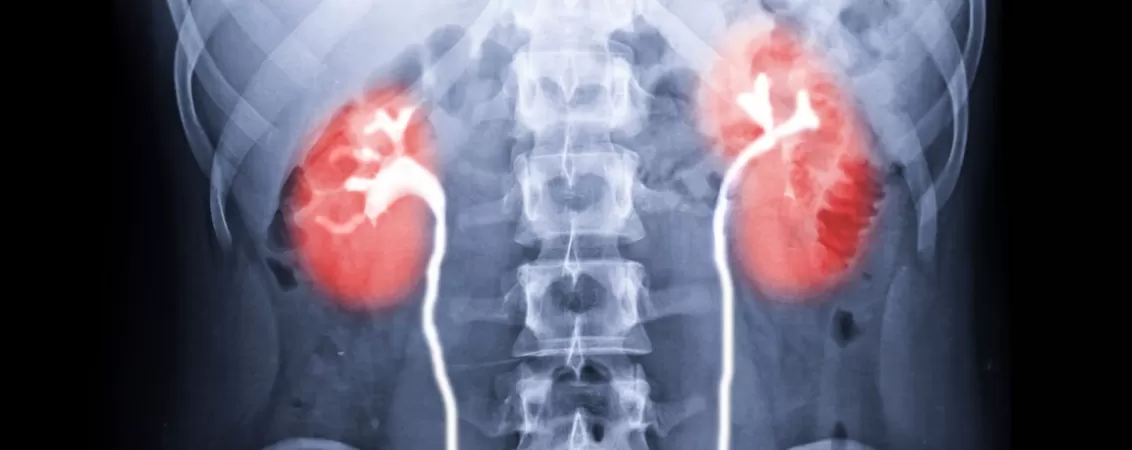

- Urografia intravenoasă (IVU) – pentru investigația rinichilor, ureterelor și vezicii urinare. Se folosește substanță de contrast iodată, administrată intravenos pentru evidențierea căilor urinare;

- pentru evaluarea funcției și structurii sistemului urinar - în urografia intravenoasă, pentru vizualizarea rinichilor, ureterelor și vezicii urinare;